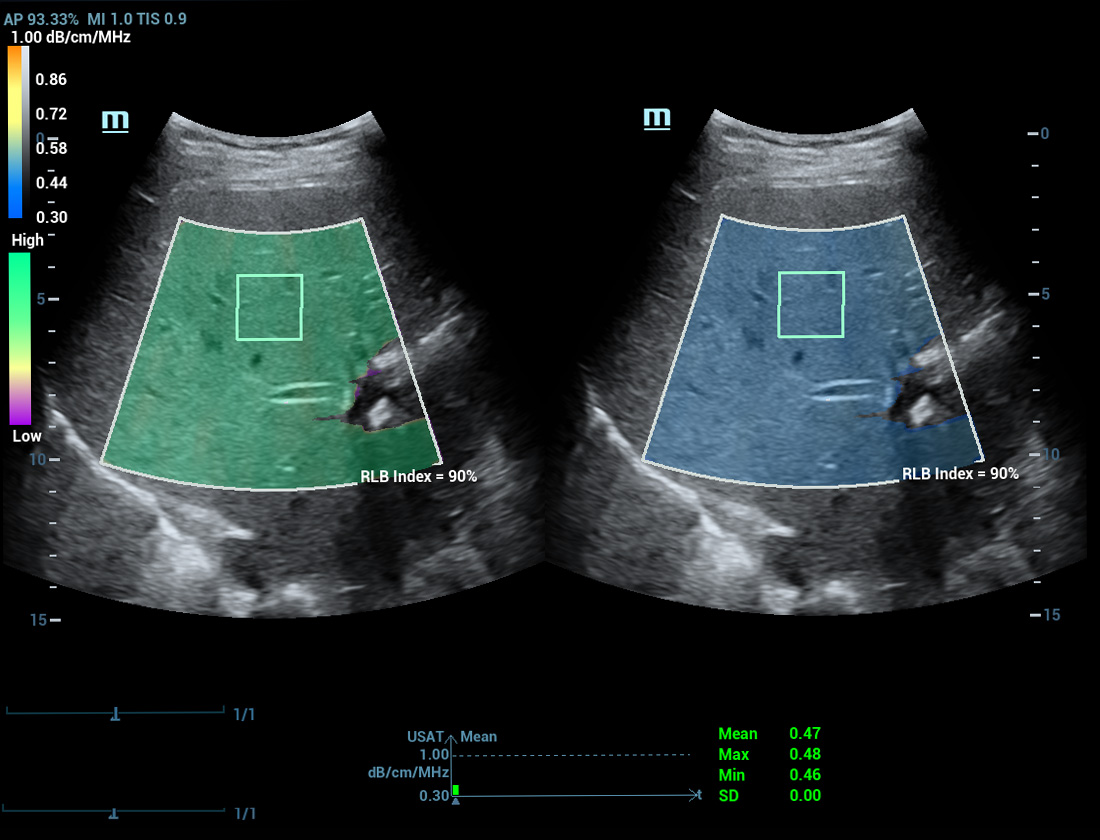

Multi-parametrisch lab voor leververvetting

Een sprong vooruit in het onderzoek naar steatose

Multi-parametrisch lab voor leververvetting

Het multi-parametrische lab voor leververvetting biedt meerdere tools voor kwantitatieve analyse die gebaseerd zijn op verschillende akoestische technologie?n. Het maakt een kwantitatieve analyse van steatose mogelijk en verbetert de gevoeligheid van de detectie van leververvetting in een vroeg stadium.

USAT S0